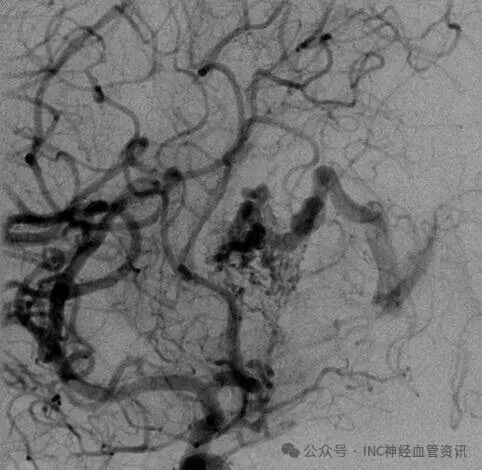

某个清晨,23岁的Anna突发剧烈头痛,紧急送医后检查显示脑室内出血,病因为透明隔区动静脉畸形。此为罕见的脑室系统病变,特征为异常血管缠结形成血管团,具有高度破裂出血风险。按照Spetzler-Martin分级系统,其病情评为5级(S2V1E0/A2B0C0),属于高风险类别。

Anna的AVM由多条动脉供血:ACA/PcaA分支、ACoA穿支和mPChA,形成复杂血管网络。首次伽马刀治疗后,血管团部分闭塞,但残留畸形血管仍构成出血威胁。